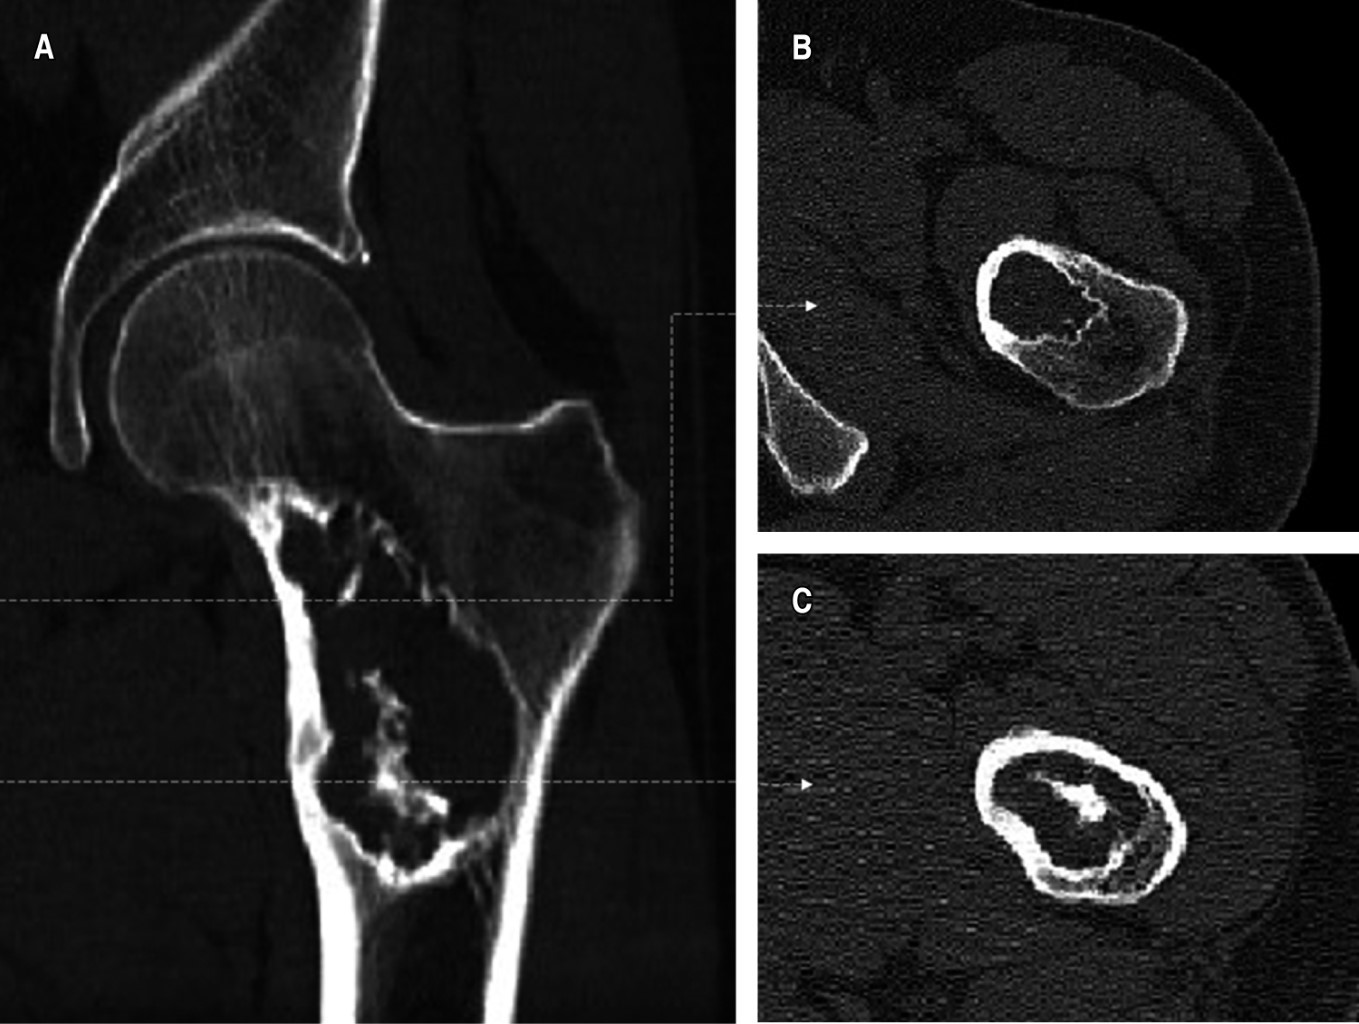

Liposclerosing myxofibroma of the proximal femur: diagnostic and therapeutic controversies. Apropos of 3 clinical cases

Introduction: The bone liposclerosing myxofibrous tumour (LSMFT) is a rare benign fibro-osseous tumor with characteristic clinical-radiological features, although its diagnosis and treatment are controversial. Material and methods: We present three patients, two women and one man, with a mean age of 46 years, diagnosed with LSMFT. The findings of the complementary imaging tests and the treatment performed are presented: observation in two patients and curettage, and the third patient was treated with curettage, grafting and surgical fixation. Results: The first two patients, after 10 and three years of follow-up, respectively, maintain the same symptoms and no progression of the lesion. Conclusions: The diagnosis of LSMFT can be assumed by clinical and imaging data without biopsy. In the absence of signs that suggest malignancy, observation is justified, limiting the surgical indication to symptomatic cases and/or those with risk of pathological fracture.

Figure 1

Figure 2

Figure 3

Figure 4

Figure 5

Figure 6

Figure 7

Figure 8

Figure 9

Figure 10